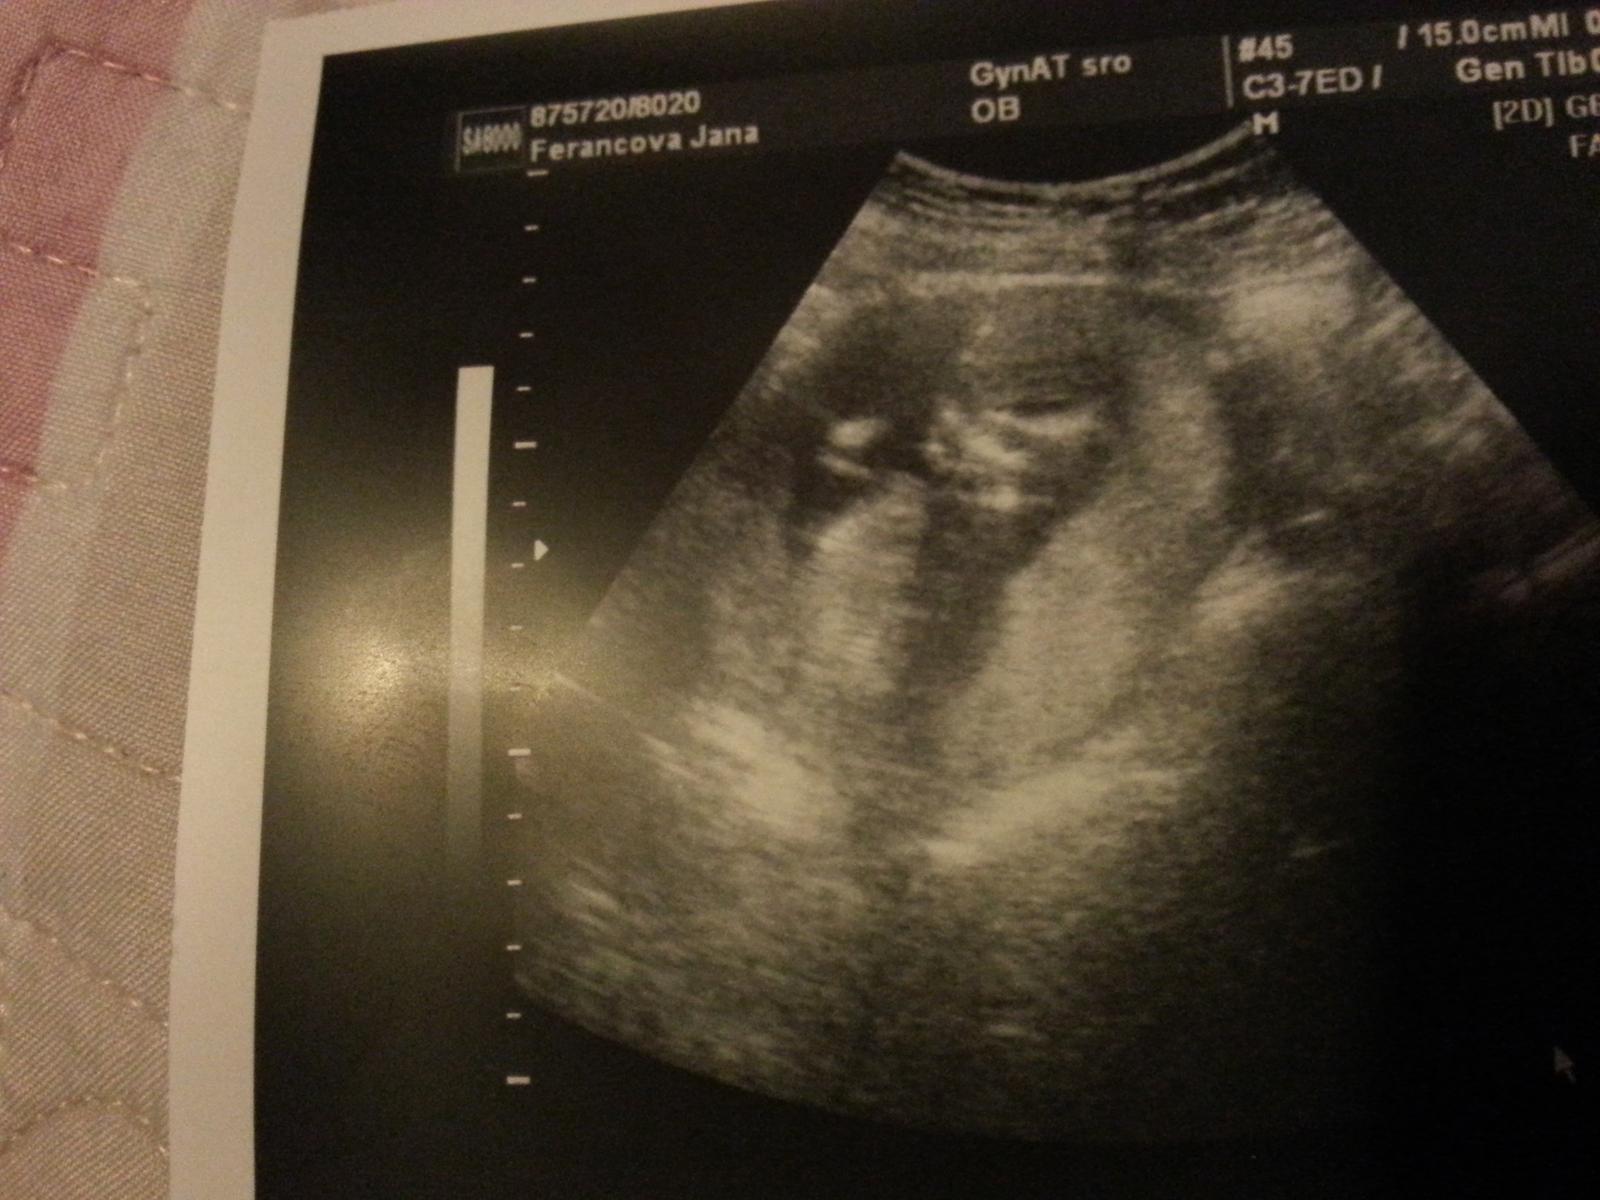

@uankab Ahoj Zuzi, cítim sa nanič, je mi brutálne zle, už asi tretí deň na skapanie, celý deň. Nemôžem nič jesť, zo všetkého ma naťahuje. Z nemocnice som sa vrátila vo štvrtok a v piatok som bola na kontrole u svojho gynekológa a ten povedal, že hematóm sa už vstrebal a bábätko krásne rastie a presne zodpovedá veľkosti podľa ovulky. Dnes som podľa menzesu 8+4 a podľa ovulky 8+5. Tak som veľmi šťastná, že to moje zlatíčko je v poriadku. 🙂

@jankaferancova , fotka bruska chyba 😉

@jankaferancova Jani, krásne fotky, blahoželám k dobrým výsledkom, len nech ste zdravučkí 🙂